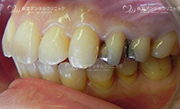

セラミックインレー

当院で扱っているセラミックインレーにはe.max(イーマックス)とジルコニアがあります。

ジルコニアインレーの方が強度がありますが、e.maxインレーの方が色が合わせやすく自然な仕上がりになる事が多いです。

ジルコニアインレーはCAD/CAMという技術により製作された物を使用し、e.max(イーマックス)はプレスいう技法で製作された物を扱っています。